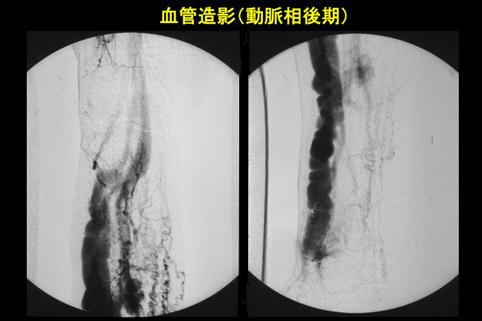

Caso de Síndrome Cowden acompañado de malformaciones arteriovenosas en membrum inferius

Lesión que asemeja tumoración/Enfermedad de Cowden

Rayos X